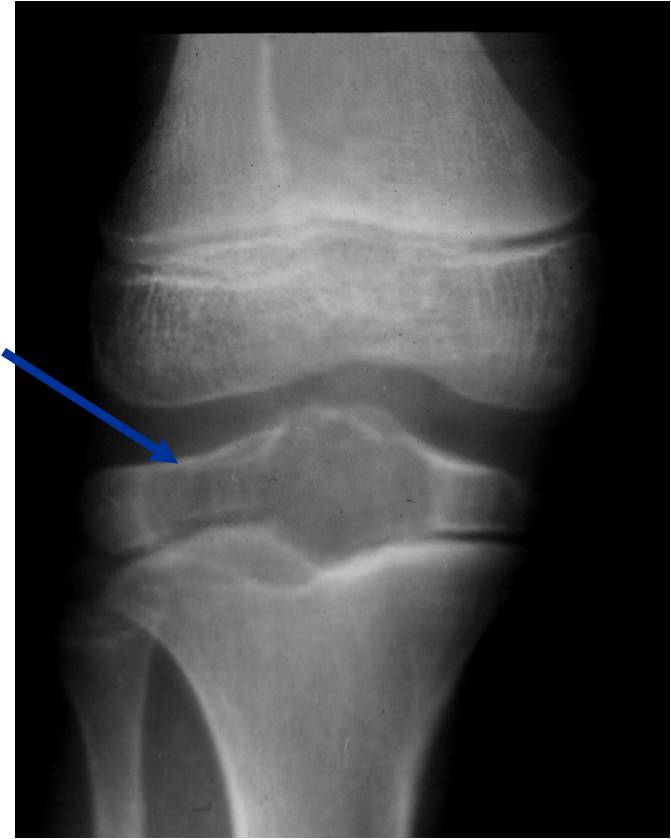

Radiographic Presentation

- Presents as a highly defined/well circumscribed geographic oval/round lytic defect

- Surrounded by rim of sclerotic bone

- Usually in epiphyseal region

- Lesion ranges from 3 cm to 6 cm diameter

- Usually radiolucent

- May have fine trabeculae and irregular calcifications

- Calcifications are often better detected with a CT scan but are not uniformly present

- Lesions may expand the bone and new periosteal bone may form

- Bony end plate, cortex, bone contour are unaffected

- (Plain x-ray appearance)

- Geographic lytic lesion IA/IB margin of sclerosis

- Usually Eccentric more often than Central in the bone

- Rarely expansile (rarely penetrates the cortex)

- Calcified chondroid matrix 30%-50% of cases

- Often better detected with a CT Scan

- Periosteal Reaction 30-50% of cases

- Usually occurs in Adjacent Diaphysis/Metaphysis since epiphysis is intraarticular and not surrounded by periosteum